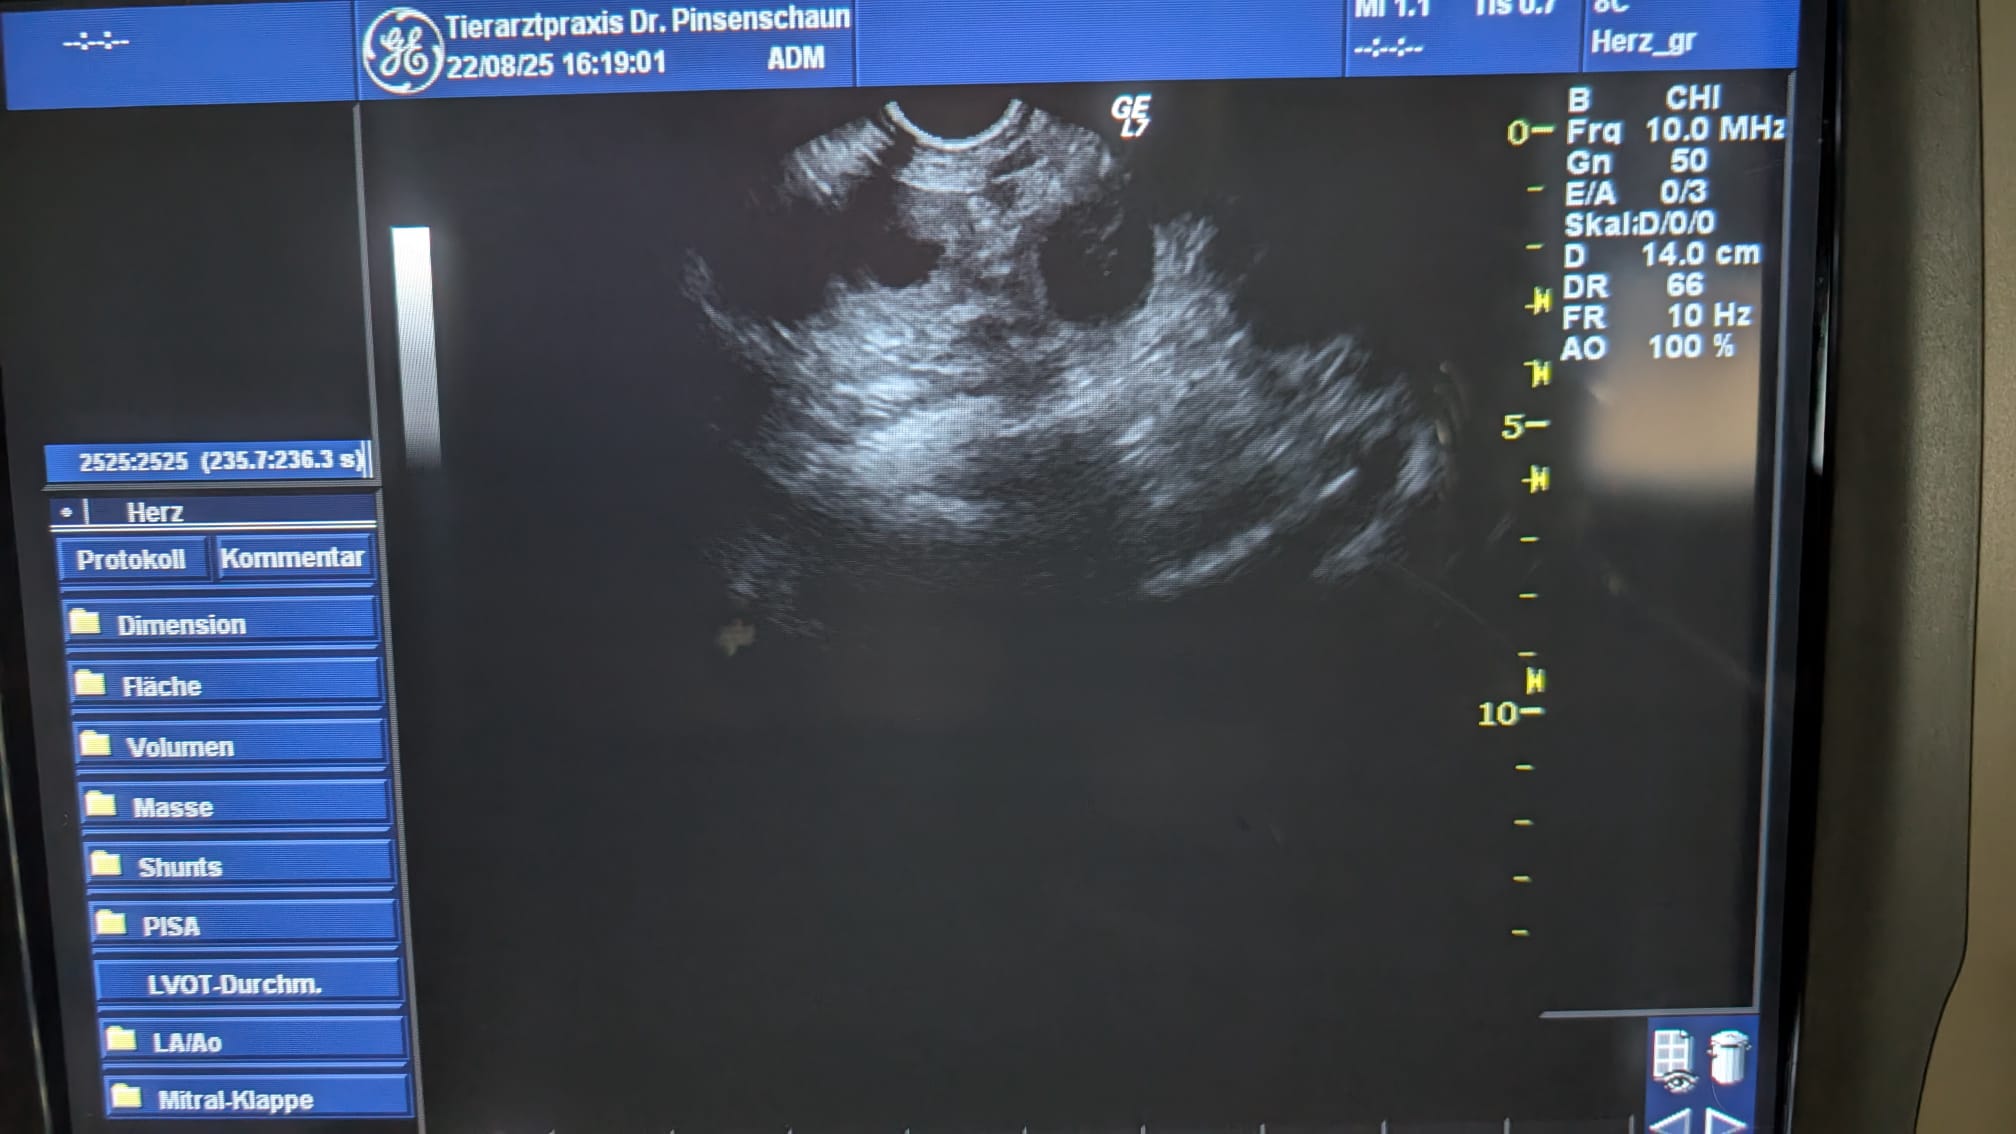

UPDATE💞 Am 22.08. waren wir bei unserem Tierarzt und das Ergebnis der Ultraschalluntersuchung bestätigt das, was uns Amalija schon gezeigt hat🙏 sie erwartet Welpen. Wir könnten nicht glücklicher sein💝